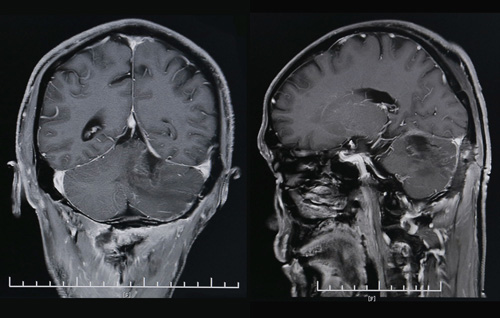

術后CT影像顯示,腫瘤已經(jīng)消失